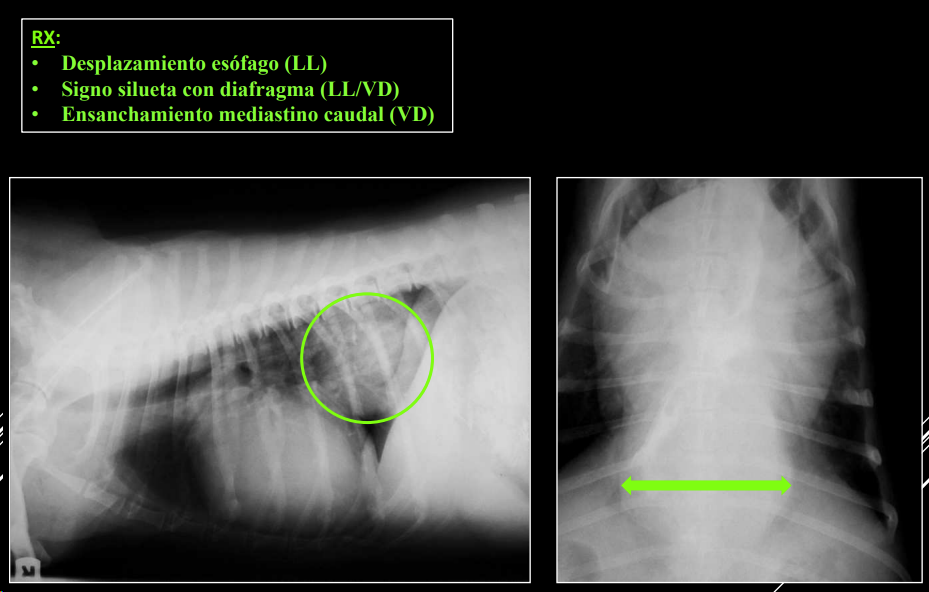

- Masas mediastínicas (craneodorsales, hilares, caudodorsales, caudoventrales, craneoventrales).

Caudodorsales: hernia paraesofágica, tumores neurogénicos, granulomas.